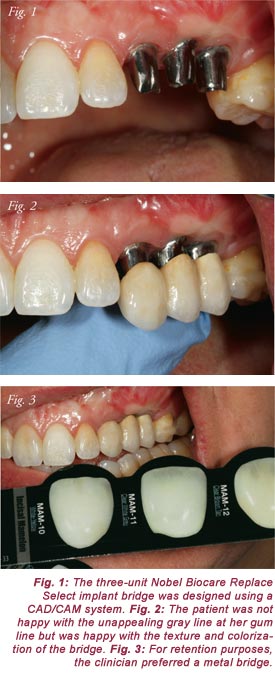

Figure 1 is a view of the Nobel Biocare Replace Select titanium implants with

CAD/CAM design before placement of the bridge. Figure 2 provides a glimpse of

the problem the patient encountered with her case. Upon examination of the fit of

the bridge, she noted an unappealing gray gum line due to bone loss. While the

porcelain texture and colorization is an excellent match, the gum area was not

acceptable to the patient because it did not look natural or aesthetically pleasing.

The clinician preferred a metal bridge because of retention and the porcelain

enamel color provided a good match with the patient's natural teeth (Fig. 3).